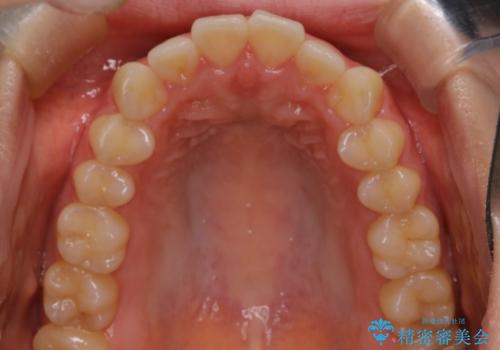

下顎前歯の叢生を短期間で改善

- 患者様は、下顎前歯のガタガタ(叢生)の改善を希望して来院されました。診断の結果、非抜歯で治療可能であると判断し、透明で目立たないインビザラインを使用する矯正治療計画を立案しました。短期間での治療を希望されていたため、IPR(歯間削合)を併用してスペースを確保しながら、効率的に歯を並べることを目指しました。

治療では、インビザラインを用いて計画的に歯を移動させ、短期間での歯列改善を実現しました。IPRを行うことで、抜歯をせずに必要なスペースを確保し、歯列全体を整えました。治療中は、装置の適切な装着時間を守ることが重要であり、患者様にも継続的な協力をお願いしました。また、歯肉や歯根への負担を最小限に抑えるため、歯の移動を慎重に管理しました。結果として、短期間で下顎前歯の叢生を改善し、自然な見た目と機能性を兼ね備えた歯列を実現できました。